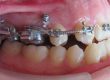

Клинични аспекти при прилагане на апарата Pendulum в смесено съзъбие

В тази статия си поставяме за цел да разискваме от клинична гледна точка позитивите и негативите при ползване на апарата Pendulum в смесено съзъбие. Ще разгледаме становищата за работа с апарата в случаите, когато са включени временните молари като опорна зона. Ще дадем какви са според нас клиничните предпоставки и индикации за използването на Pendulum в смесено съзъбие. Ще разгледаме терапевтичния протокол на няколко клинични случая, решени с прилагането на този апарат. Натрупаният от нас опит показва, че независимо кои зъби са в опорната зона се получава дистализиране на горни молари, но има разлики в не са значителни и не се отразяват негативно на основния ефект от действието на апарата Pendulum. Затова препоръчваме неговото ползване във всяка възраст и дентиция.